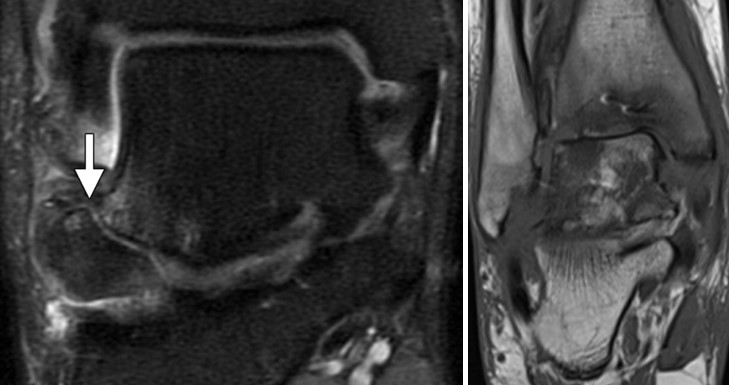

Магнітно-резонансна томографія (МРТ) має високу чутливість у виявленні окультних переломів, кісткового набряку та ранніх ознак аваскулярного некрозу. МРТ особливо корисна при підозрі на ушкодження хряща, остеохондральні ушкодження та при подальшому моніторингу загоєння.